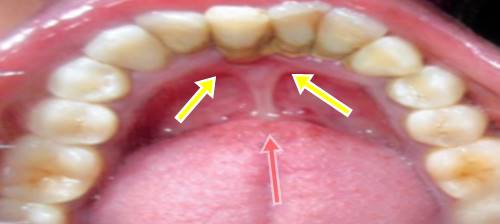

Diş eti çekilmesi tıp dilinde gingival resesyon olarak tanımlanmış olan dişin diş kökünü saran pembe diş eti dokusundan geriye doğru çekilmesine denir. çocuklar diş eti iltihabı söz konusu olduğunda ebeveynleri kadar risk altındadır. Bunlardan ilki dişlerde meydana gelen çürümesi enfeksiyon ve diğer hastalıkların tedavi edilmesidir. Diş eti bozulmaya başladığında ilk önce karşılaşılan sorun diş eti kanamasıdır.

Diş eti çekilmesi diş etinin diş kökü üzerinden çekilerek kök yüzeyinin açığa çıkmasıdır. Ağız temizliğinin iyi yapılamıyor olması diş etlerinde mevcut olan yapısal bozukluklar hatalı fırçalama tekniklerinin uygulanması diş gıcırdatılması kalem ısırma gibi alışkanlardan kaynaklı oluşabilmektedir. Diş eti çekilmesi tek bir dişte veya pek çok dişte aynı anda görülebilir. Dolayısıyla diş etleri dişlerden çekilir ve kökleri açığa çıkarırlar bu.

çünkü sorunlara en kısa sürede müdahale yapılmazsa ilerleyen zamanlarda daha büyük problemler. Diş eti çekilmesi diş etinin kök yüzeyini açıkta bırakarak yer değiştirmesidir. Diş etlerindeki çekilmenin bir sebebi de tır. Diş eti iltihabı diş eti hastalığının en erken aşamasıdır ve national institute of dental and craniofaciol research e göre doğru tedaviyle durumu tersine çevirmek mümkündür.